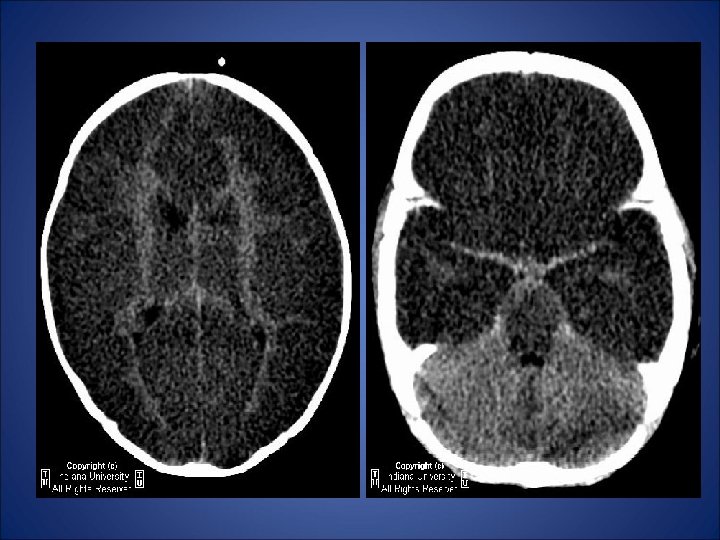

• A three month old boy in emergency room • Who survived a cardio-pulmonary arrest • NCCT scan of brain was performed …

• Reversal of the gray/white matter densities is noted diffusely, with decreased density of cerebral cortical gray matter and relatively increased density of the thalami, brainstem, and cerebellum. The ventricles appear relatively decompressed, with diffuse loss of sulcation, compatible with diffuse cerebral edema. The suprasellar cistern appears effaced, suggestive of downward transtentorial herniation.

DIAGNOSIS: DIFFUSE HYPOXIC-ISCHEMIC CEREBRAL INJURY

• Term infants suffering profound perinatal asphyxia show a characteristic sequence of imaging findings. • Initial CT scans may be normal or minimally abnormal. • Severe generalized cerebral edema ensues over 24 to 48 hours and is seen as diffusely low density brain, often with a “reversal” sign. • Here, the cerebellum appears hyperdense compared to the abnormally low density cerebral hemispheres. • Gray-white matter differentiation is lost. • Hemorrhagic cortical necrosis with secondary calcification can often be observed within a few days after the hypoxicischaemic insult. • Severe atrophic changes are common in surviving infants.

1. Initial axial CECT scan 24 hours after delivery shows diffuse low density in the cerebral hemispheres. The cerebellum appears comparatively hyperdense, the so called- reversal sign. 2. NCCT scan after 5 days shows enlarged ventricles and low density hemispheres without gray-white matter differentiation.

Key Points: • Hypoxic-ischemic cerebral injury is a major cause of morbidity in children • CT reversal sign - represents diffuse, anoxic/ischemic cerebral injury. – Diffusely decreased density of cortical gray and white matter with decreased or lost gray/white matter interface (reversal of gray/white matter densities – Relatively increased density of thalami, brainstem, and cerebellum. • Carries poor prognosis and indicates irreversible brain damage. • Particularly susceptible tissues to hypoxic-ischemia include the neocortex, basal ganglia nuclei, portions of cerebellar cortex, and brain stem. • Discrepancies between clinical history and severe insult should raise possibility of nonaccidental trauma.